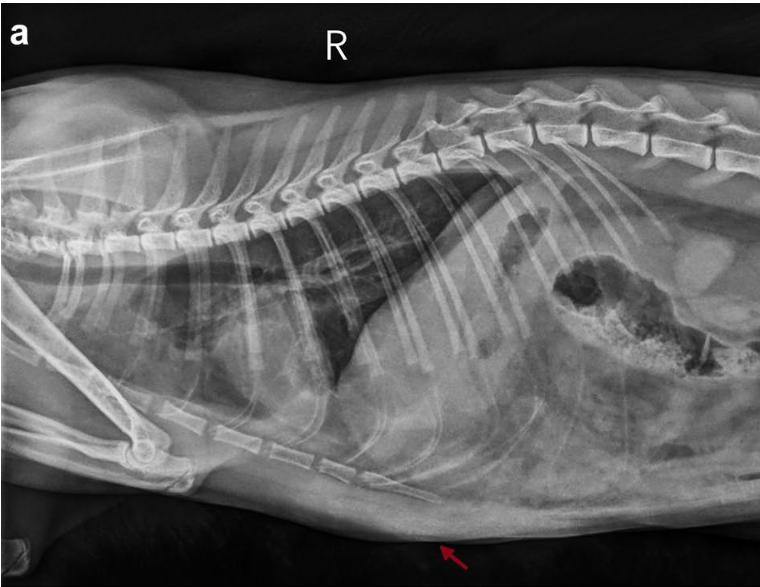

옆구리 탈장(Paracostal hernia)은 복벽의 일부인 외복사근과 복횡근이 갈비뼈나 늑연골 부착부위에서 찢어지면서 복강 내 장기가 피하 공간으로 탈출하는 상태를 말합니다. 주로 교통사고나 다른 동물과의 싸움 등 외상으로 인해 복압이 급격히 상승하면서 발생합니다.

- 결과 1: 횡격막 탈장의 높은 동반율 가장 주목할 만한 결과는 옆구리 탈장이 확인된 고양이 19마리 중 12마리(63%)에서 횡격막 탈장이 함께 발견되었다는 점입니다. 이는 옆구리 탈장 진단 시 횡격막의 상태를 반드시 함께 평가해야 함을 시사합니다.

따라서 옆구리 탈장이 의심되는 외상 환자의 경우, 수술 전 방사선 검사 등 영상 진단을 통해 횡격막의 연속성을 면밀히 평가해야 합니다. 또한, 수술 시에는 탈장 부위에 국소적으로 접근하기보다는 복부 정중선 절개를 통해 복강을 열고, 횡격막 전체를 시각적으로 직접 확인하여 손상 여부를 평가하는 것이 강력히 권장됩니다.